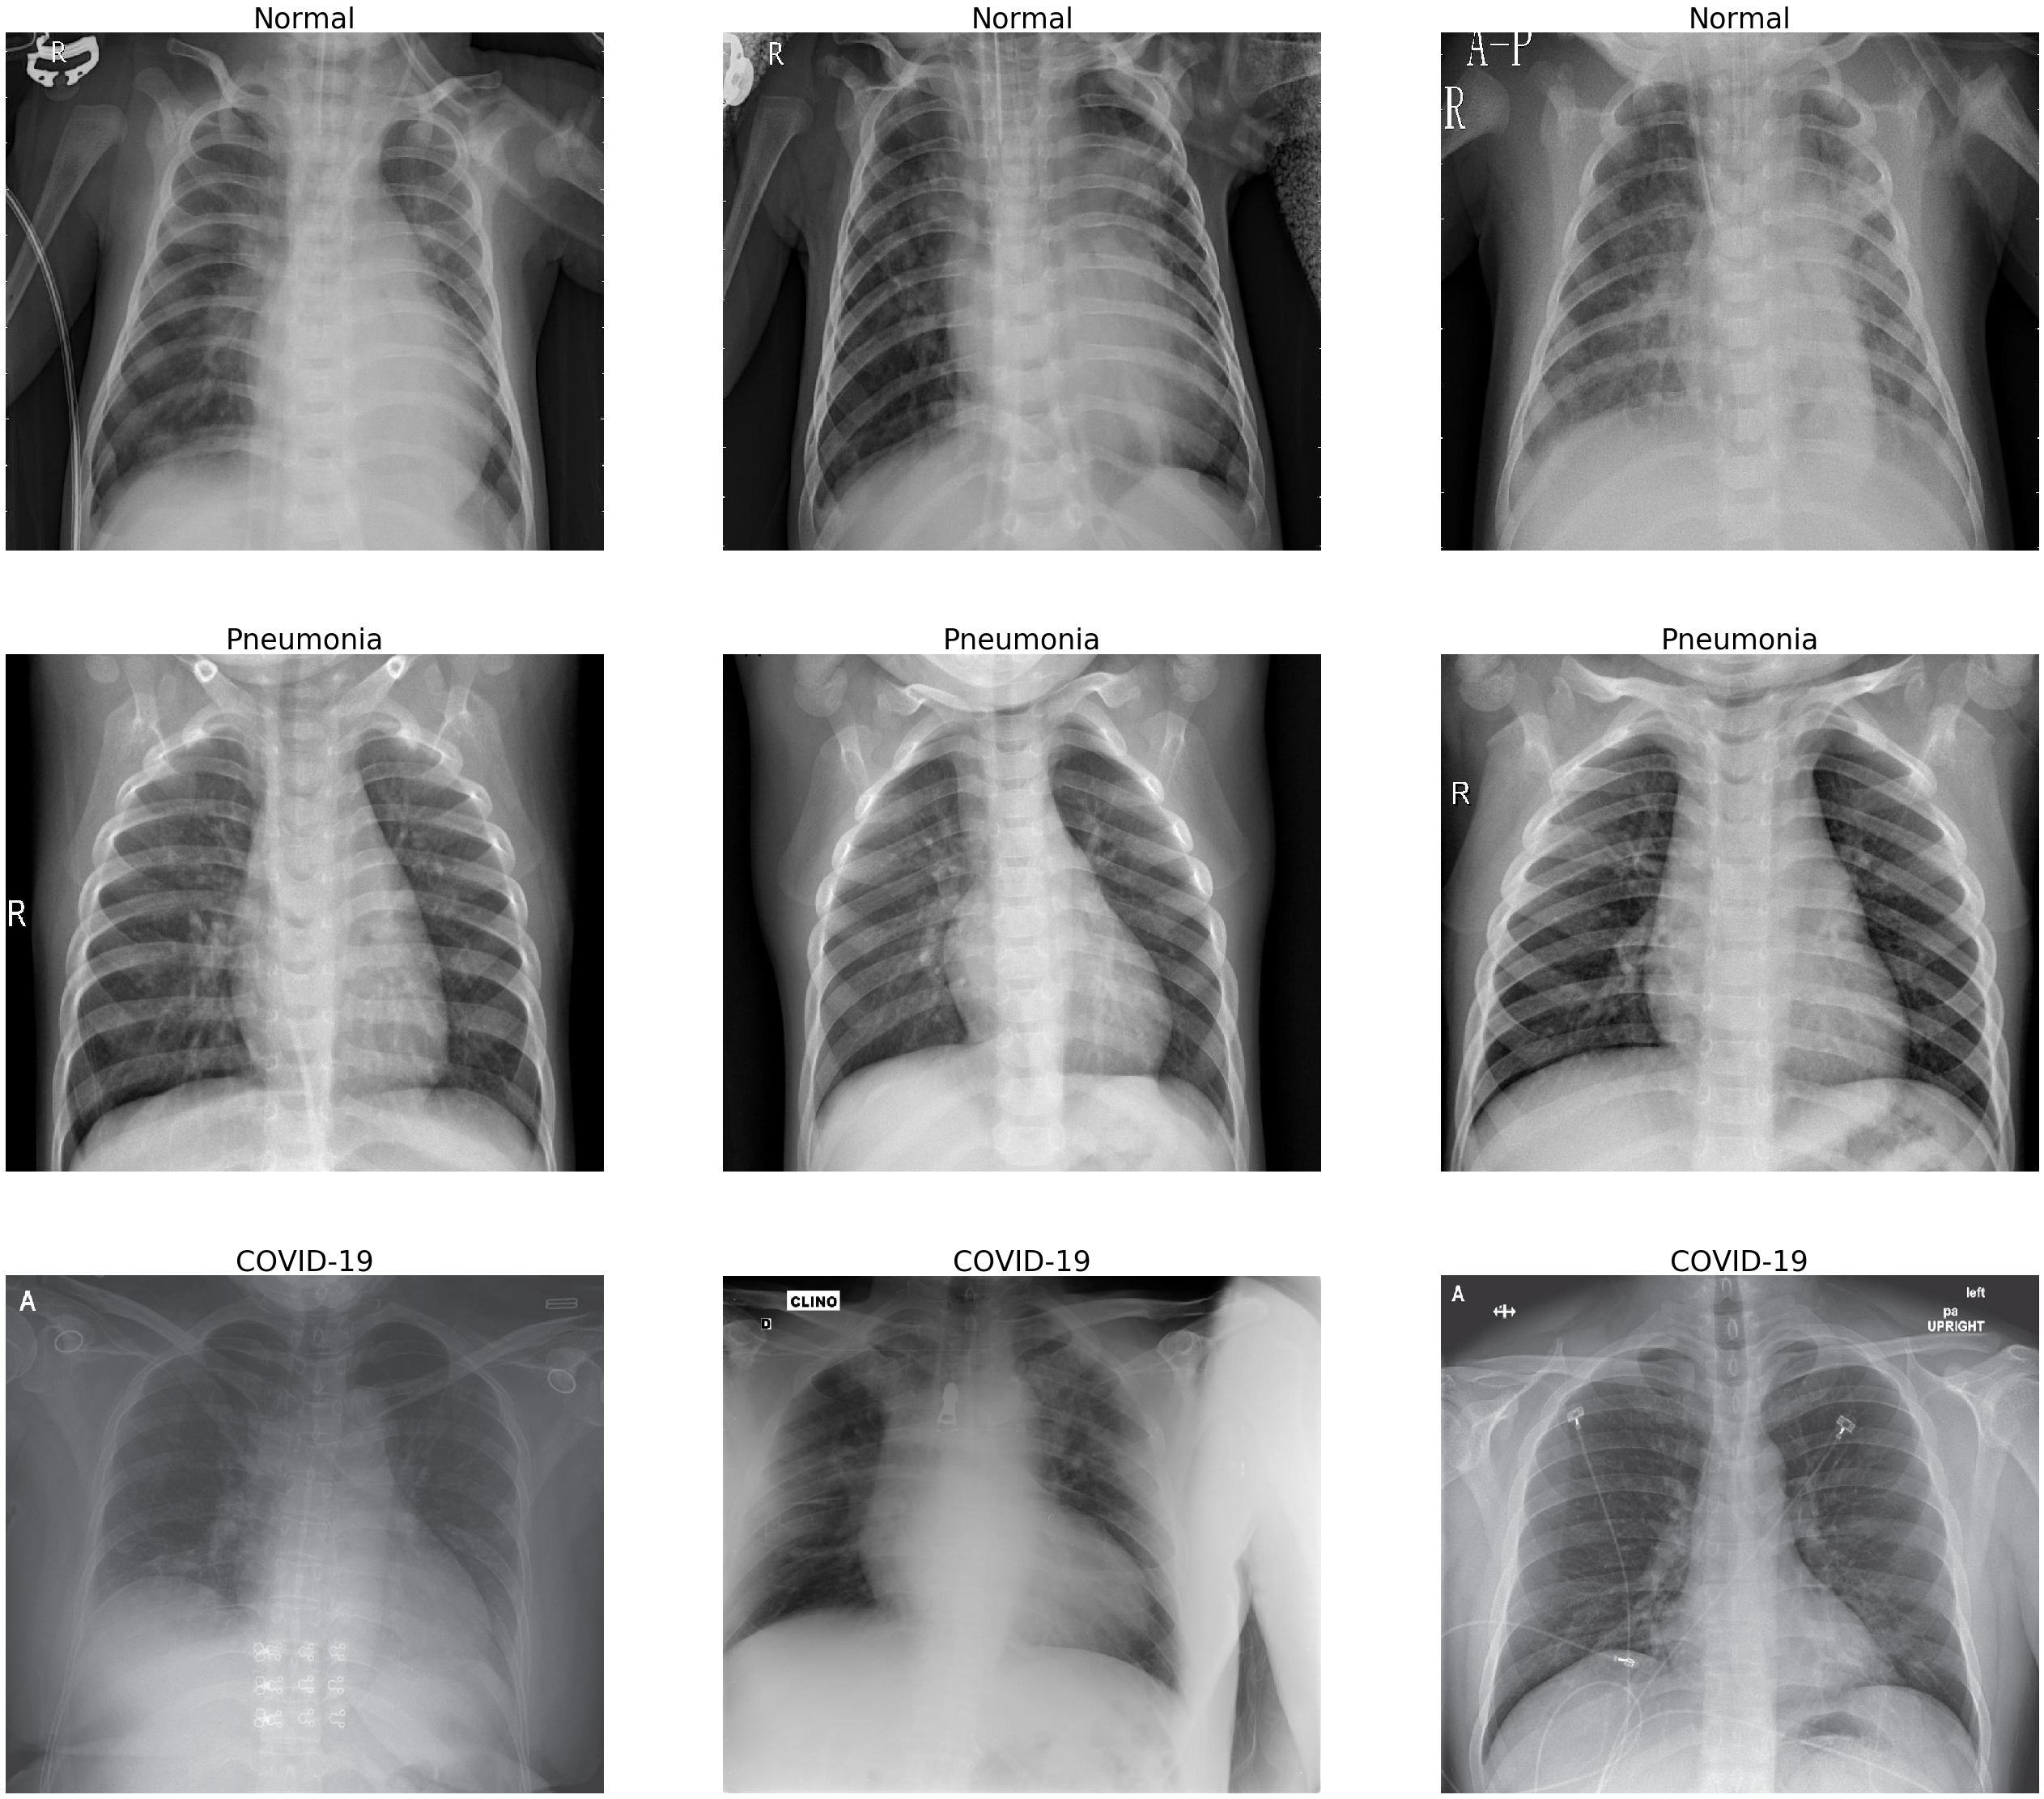

Comparison Of Different Chest X Ray Of Normal Covid 19 Patient S Download Scientific Diagram

www.researchgate.net